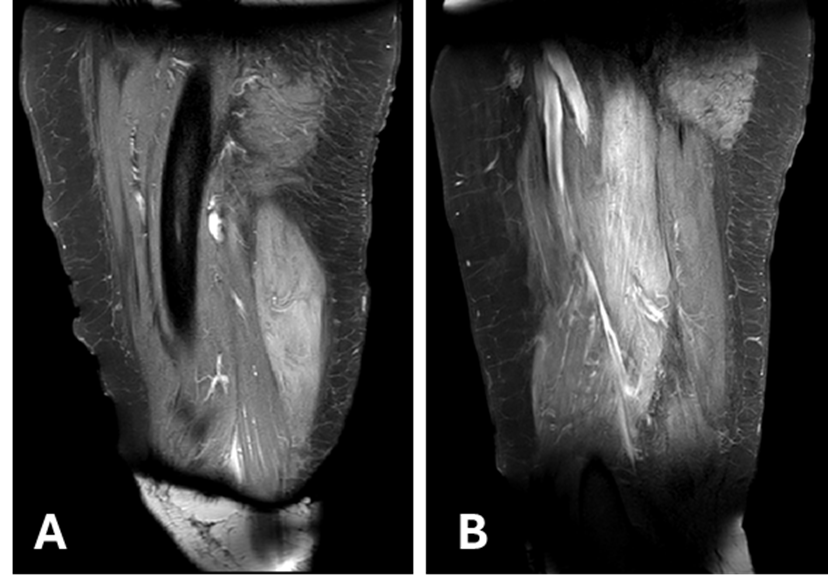

Chronic Quadriceps Lesion with Peroneus Longus Autograft - A Case Report

Diego Escudeiro de Oliveira, Bruno Arjonas Bononi, Juliano Malpaga, Marcos Vaz, Pedro Baches